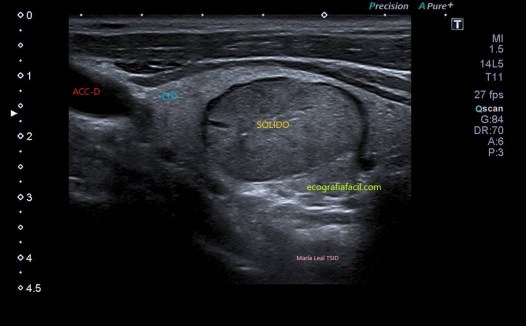

SÓLIDO:

Sólido

COMPOSICIÓN: Sólida                             2

ECOGENICIDAD: Hiperecoica                  1

FORMA: Más ancho que largo                 0

MARGEN: Liso                                          0

NO FOCOS ECOGENICOS:                          0

3 puntos